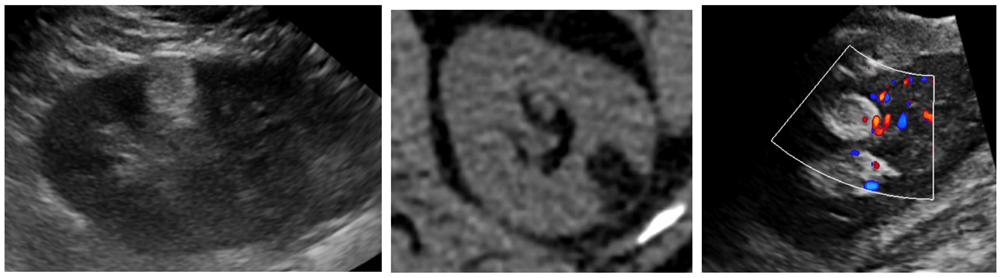

Contrast enhanced ultrasound (CEUS) with microbubble injection is an emerging tool in small renal mass characterisation and serves to identify abnormal vascularity. Although CEUS cannot differentiate malignant from benign renal masses, for instance RCC from oncocytoma, CEUS can reliably differentiate simple cystic lesions from solid vascularised lesions (Figure 4) [6]. CEUS is particularly useful for assessing septal vascularity within complex cystic lesions and problem solving in cases where CT / MRI assessment of small renal lesions proves indeterminate.

Figure 4: Mildly hyperechoic renal lesion on US (left).

Avid enhancement following microbubble injection (right).

Courtesy of Dr Cherian George, UHNM NHS Trust.